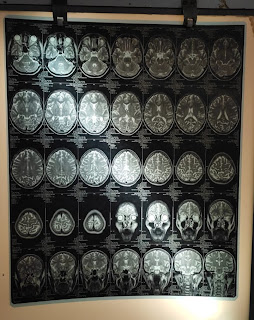

CT brain was done showed left frontal lobe edema.